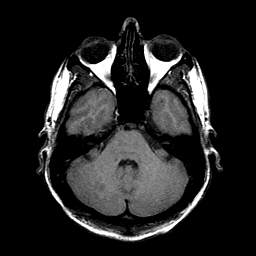

Sarcoma, MR Study #1 mr-t1 -- Slice #5

[Home][Help][Clinical] Slice 5